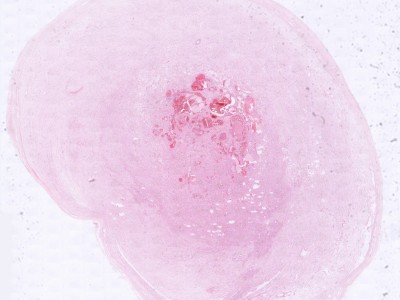

Schwannoma Schwannoma

ingescande coupe (zoom) ingescande coupe (zoom)

Bron hoge resolutie PA-foto's: Kevin Kwee en Afdeling Pathologie MUMC. Klik op de afbeelding om in te zoomen.